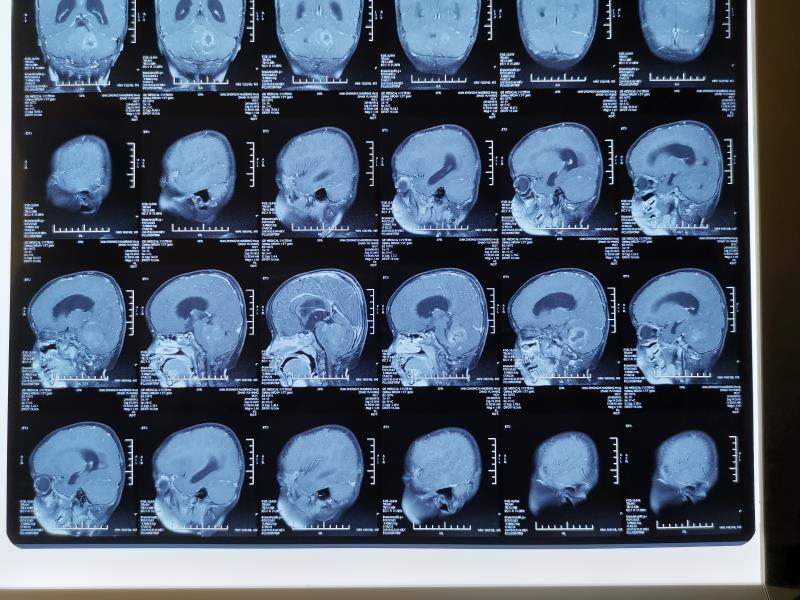

室管膜瘤_室管膜瘤_介绍_症状表现_检查_治疗方式 - 好大夫在线

图片尺寸3968x2976